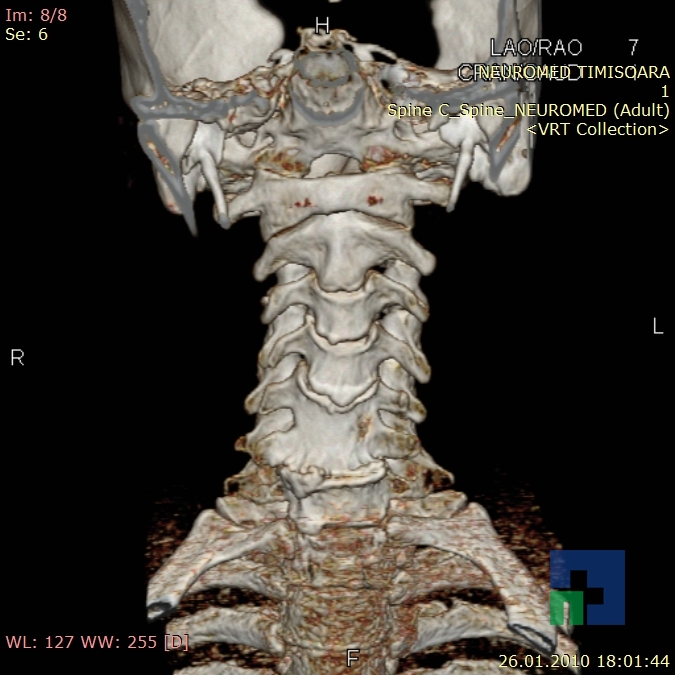

- Diagnosticul traumatismelor de bază de craniu

- Diagnosticul fracturilor: